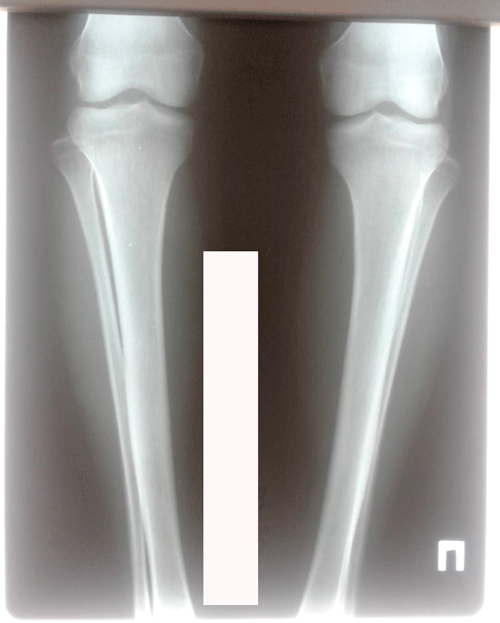

Исходник - 26 лет.

Варусная деформация голеней.Ротация с обеих сторон.

Дата операции - 27.03.2019г.

Рентген перед фиксаией